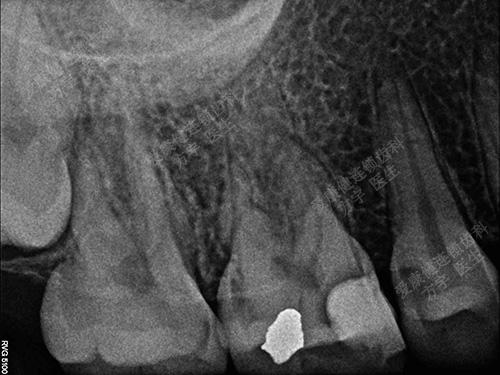

术后